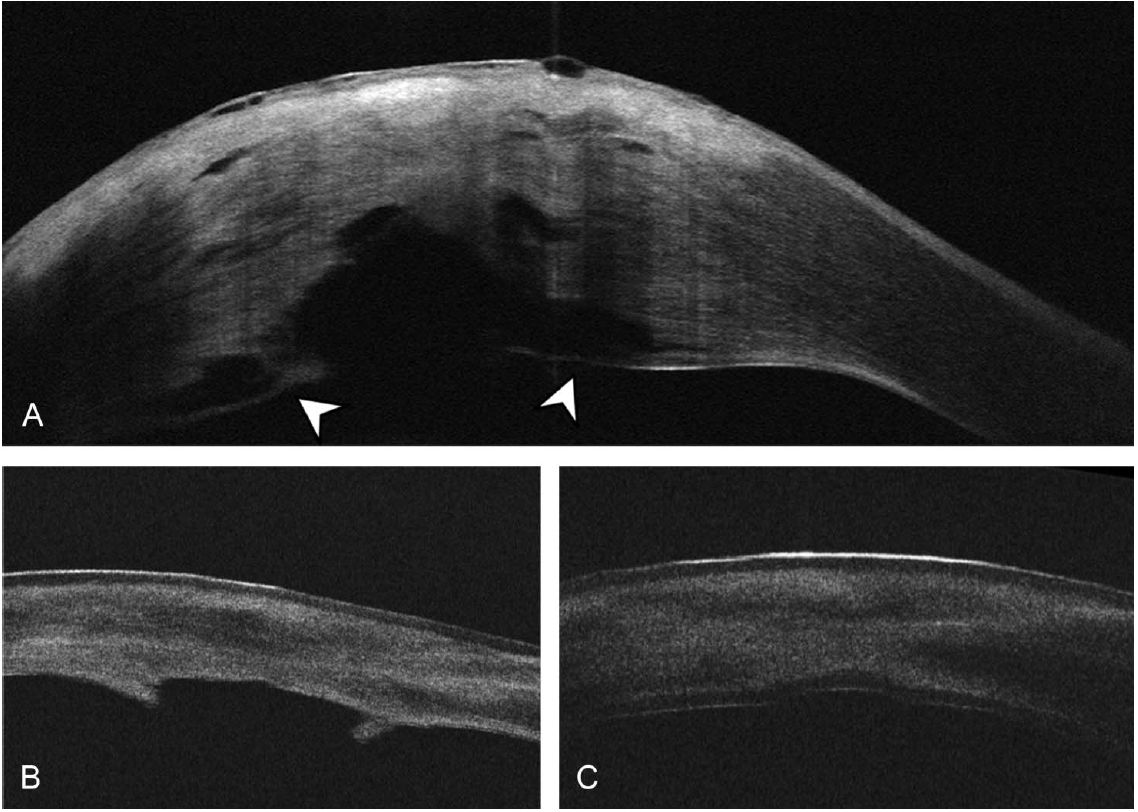

A, AS-OCT of the cornea at 10 days after presentation showing reattachment of DM. Shadowing from the stromal obscures part of the posterior cornea edema. In the visualized portion of the posterior cornea, a water cleft separates a thin layer of posterior stroma and DM, from the remaining stroma (arrowheads). B, AS-OCT 5 weeks after presentation demonstrates improving corneal edema with persistent haze, an irregular contour of the central posterior cornea, and protrusions of tissue. The contour of the central posterior cornea is irregular. C, AS-OCT 1week after ultrathin DSAEK confirms a well-attached graft.